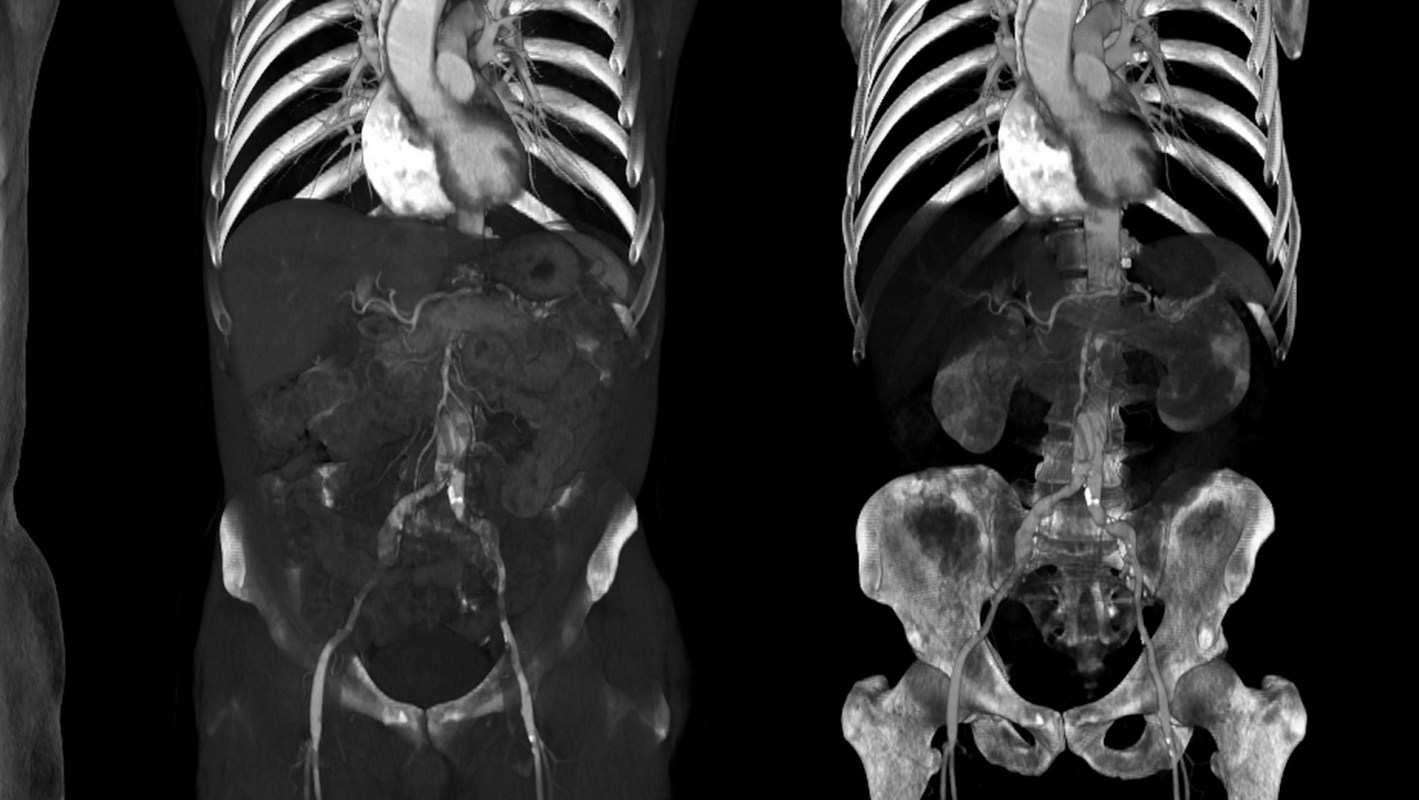

Scientists at Rush University Medical Center in Chicago are investigating how joint replacements can lead to microplastic debris in patients, which can cause implants to fail due to a local foreign-body response to these particles. They say they have found metal and plastic particles throughout the body, from the lymph nodes to the liver, heart, and bone marrow.